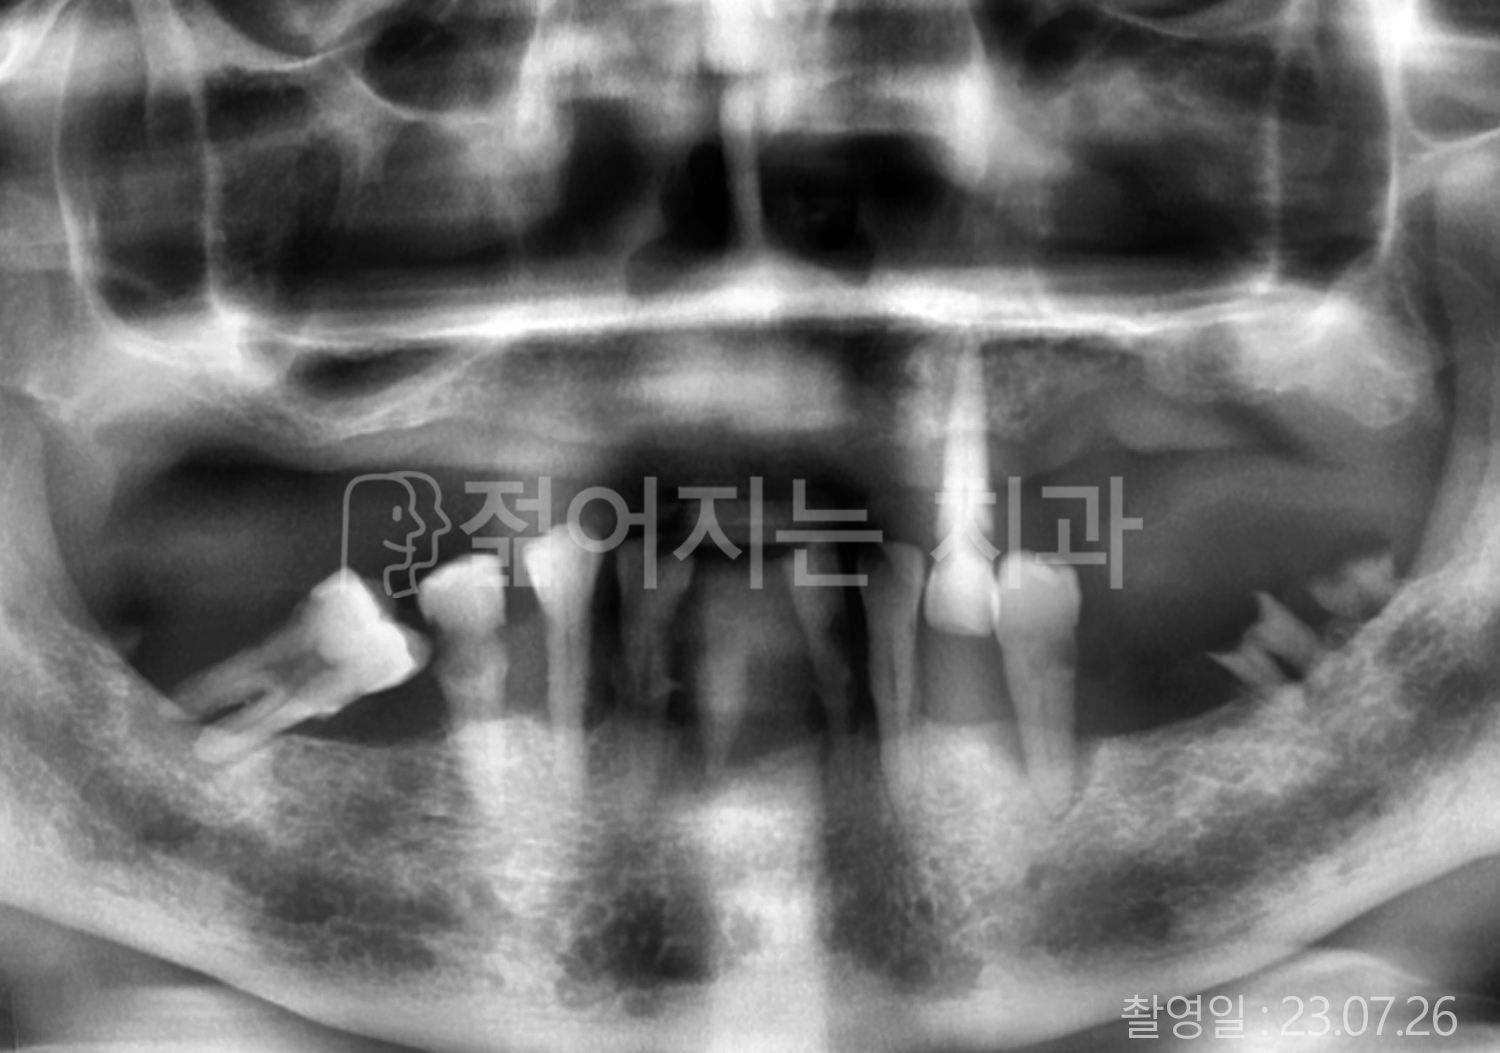

• 60대 전체치아 10개 이상 임플란트

• 50대 전체치아 10개 이상 임플란트

• 70대 고혈압, 암, 갑상선 질환 전체치아 10개 이상 임플란트

• 60대 고혈압, 당뇨, 고지혈증 전체치아 10개 이상 임플란트

• 40대 당뇨 전체치아 10개 이상 임플란트

• 70대 전체치아 10개 이상 임플란트

• 60대 당뇨 전체치아 10개 이상 임플란트

• 70대 고혈압, 당뇨 전체치아 10개 이상 임플란트